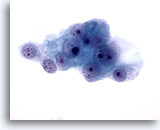

画像 4

肝FNA – 良性肝細胞

反応性変化を来した肝細胞。核は大小不同で、二核を有しています。

40倍

画像 4

肝FNA – 良性肝細胞

反応性変化を来した肝細胞。核は大小不同で、二核を有しています。

40倍